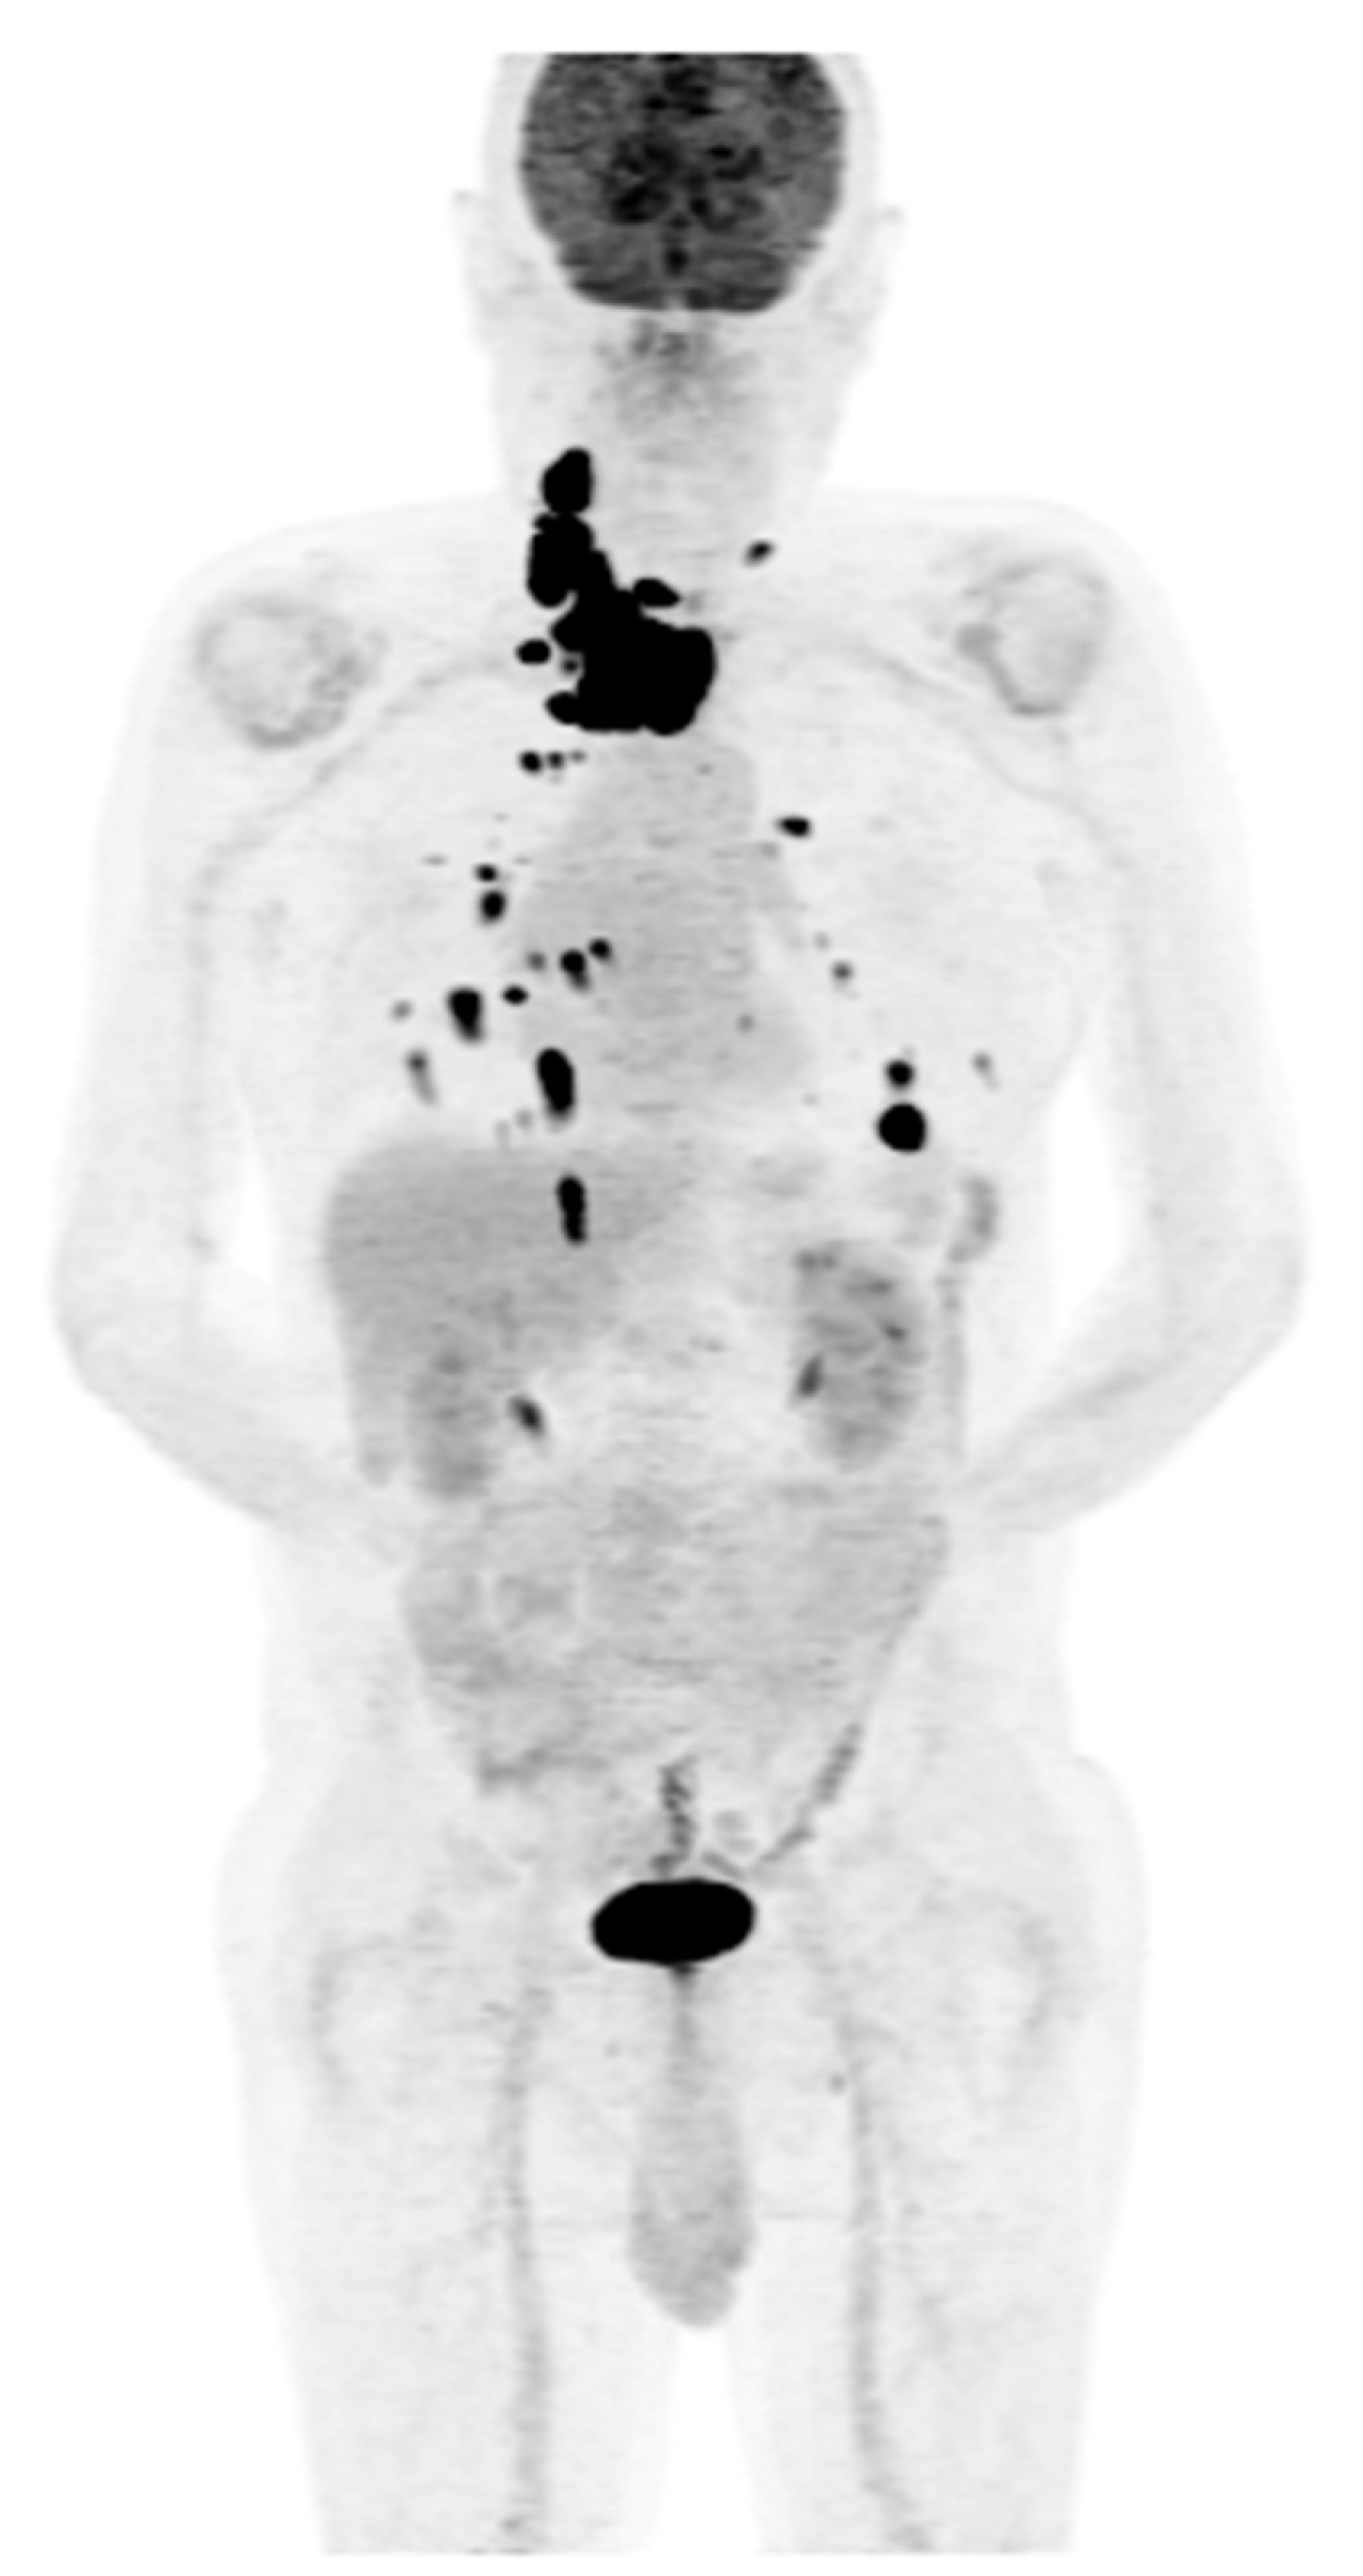

Figure 6.

PET/CT with [18F]FDG (a) Maximum-intensity projection (MIP). (b) Axial fusion projection. Multiple metastatic lesions are visible in the mediastinal lymph nodes, with a small metastasis to the left pelvic bone and an extensive tumor in the left scapula (red arrow) is visible with high [18F]FDG accumulation (the lesion was confirmed using a core needle biopsy as metastasized DTC). The patient was disqualified from surgical treatment and qualified for TKI therapy (initially sorafenib, then cabozantinib due to progression). The patient died in December 2023 (i.e., 51 months after the DTC diagnosis and 37 months after the confirmation of non-iodine-avidity disease).